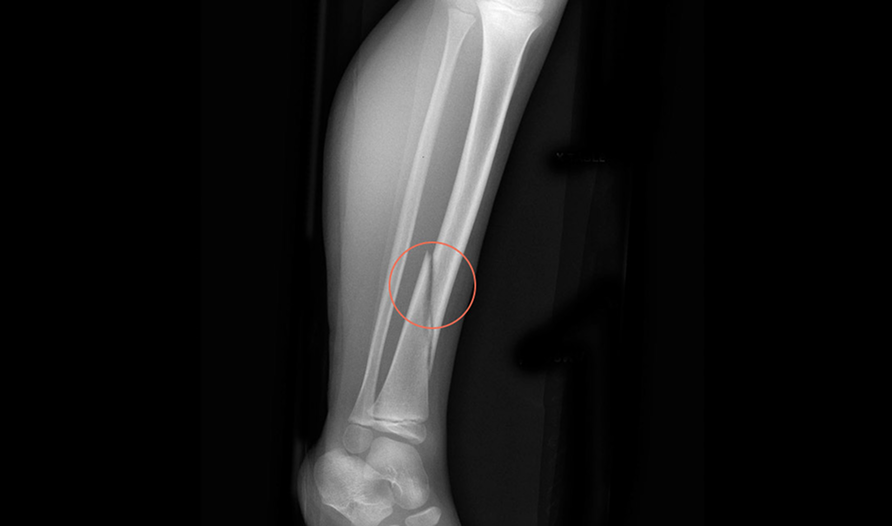

Rbfracture™

AI-powered, automatic detection of trauma-related findings

Hip fractures are the most common disabling injury and cause of accidental death in older people.

It is estimated that between 2-9% of hip fracture cases are missed